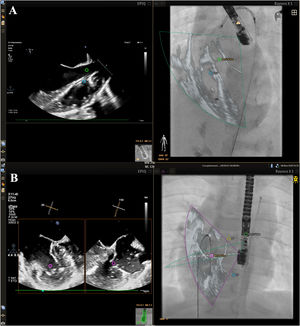

EFF imaging was successfully performed in all 8 ASD cases, and in 1 patient with a complex separated double ASD, EFF imaging offered enhanced guidance for crossing both defects separately, enabling improved manipulation and repositioning of the prosthesis, as well as the simultaneous deployment of 2 ASD occluders (figure 1A,B). EFF imaging was also successfully used in all 10 cases of VSD, enabling assessment of the size, position, and rims of the defects. EFF imaging also facilitated precise VSD crossing using markers (figure 2A) and ensured accurate prosthesis placement (video 1 of the supplementary data). In the case of a 2-year-old patient with congenitally corrected transposition of the great arteries with dextrocardia, a complex diagnostic catheterization was performed guided by EFF imaging. Given the atypical cardiac anatomy and spatial orientation, which complicates visualization and interpretation and the mirrored positioning of the heart and associated structures, EFF imaging played an important role in helping the interventional cardiologist understand the anatomy and the spatial orientation to better guide the catheterization procedure (figure 2B, video 2 of the supplementary data). EFF imaging was also successfully employed for an atrioseptostomy in a 3-year-old patient with nonoperated corrected transposition of the great arteries and VSD.

Two-dimensional echocardiography-fluoroscopy fusion (2D EFF) imaging. A: ventricular septal defect (VSD) closure in a (9kg) patient. Mid-esophageal view of the left ventricular outflow tract. Markers were positioned on the VSD and at the aortic valve level, facilizing crossing the VSD by a sheath. B: catheterization of a 13kg patient with congenitally corrected transposition of the great arteries and dextrocardia, showing markers to indicate the spatial positions of all valves. The guidewire can be clearly seen crossing the mitral valve into the left ventricle from the inferior vena cava and right atrium.